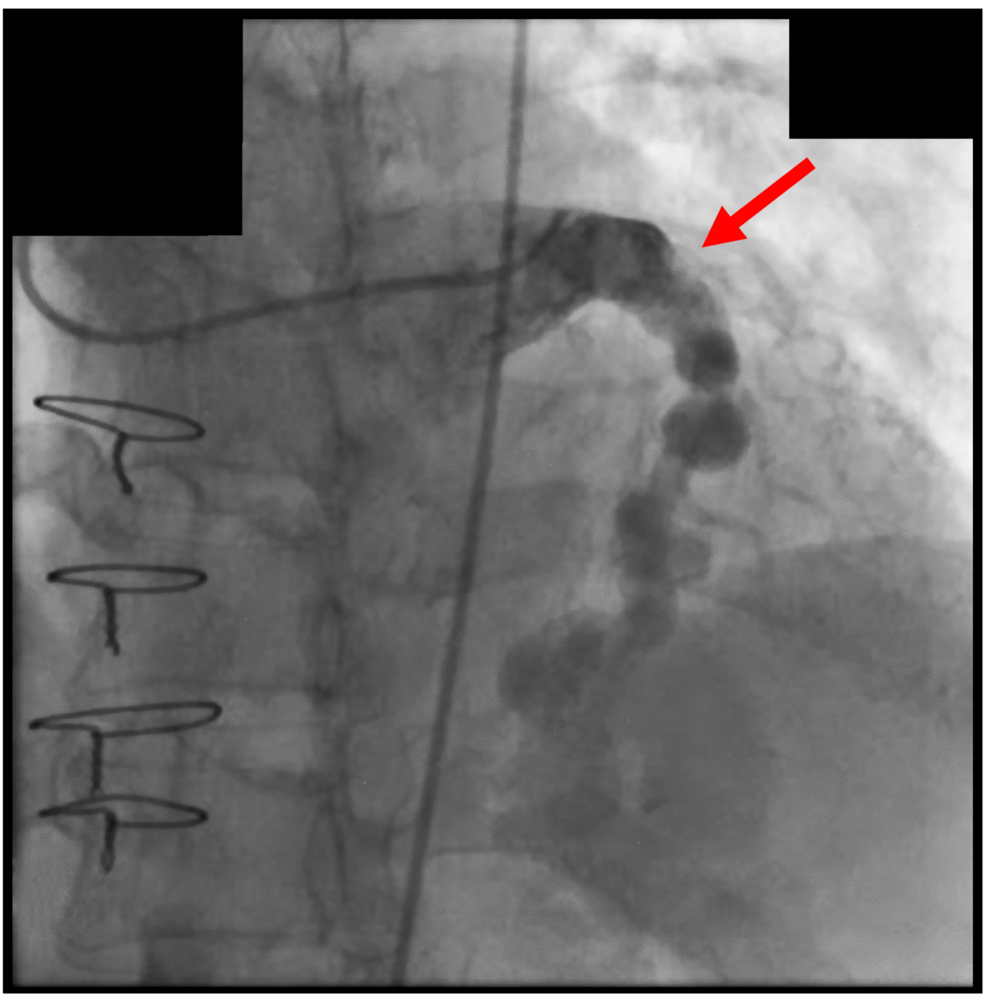

The Curet case demonstrates the feasibility of complex reimplantation techniques even in challenging scenarios. Successfully navigating a reoperative aortic root replacement with concurrent aneurysmal left main coronary artery reimplantation requires meticulous surgical planning, advanced imaging, and a deep understanding of aortic biomechanics. However, reimplantation, while a significant advancement, remains a complex and invasive procedure. It’s a testament to surgical skill, but not necessarily a long-term solution to the underlying problem of tissue degeneration.

Aortic reimplantation is a surgical procedure where a portion of the aorta, including the aortic valve and root, is replaced with a graft. In complex cases, like the one described by Curet, this can involve reimplanting the coronary arteries as well.